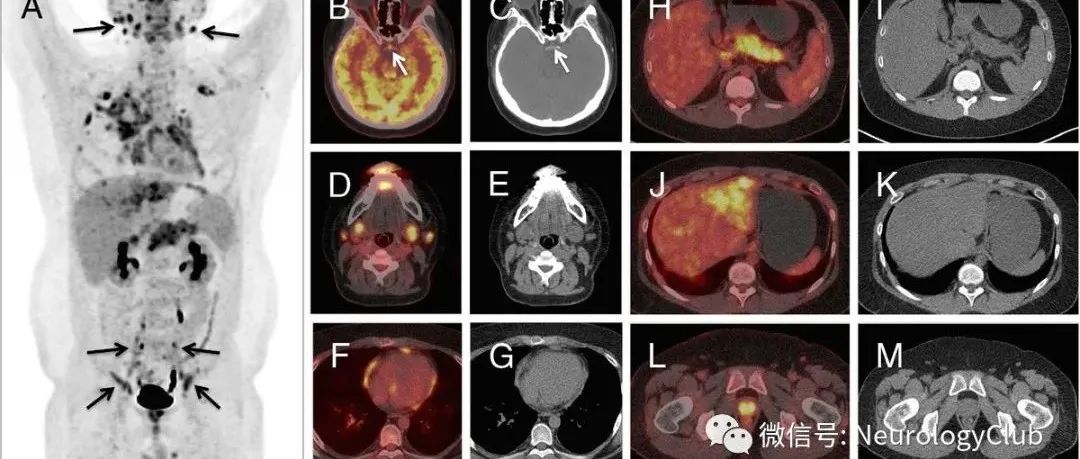

神经指南:IgG4相关性疾病诊治中国专家共识

导读IgG4相关性疾病(immunoglobulin-G4 related disease,IgG4-RD)是近年来新被定义的一种由免疫介导的慢性炎症伴纤维化的疾病,主要组织病理表现为以IgG4+浆细胞为主的淋巴、浆细胞浸润, 并伴有席纹状纤维化、闭塞性静脉炎和嗜酸性粒细胞浸润。该病几乎可累及身体的各个部位,少数患者仅有单个器官受累,而大多数患者则同时或先后出现多个器官病变。显著升高的血清IgG4水平和肿块样病灶是本病最常见的临床表现,肿块样病变和持续性免疫炎症反应导致的纤维化可对受累脏器及其周围组织造成压迫和不可逆的损伤,甚至器官功能衰竭。此外,本病因肿块样病变易被误诊为肿瘤,导致部分患者接受不必要的手术治疗或放化疗。...

神经病学俱乐部 2022-09-16